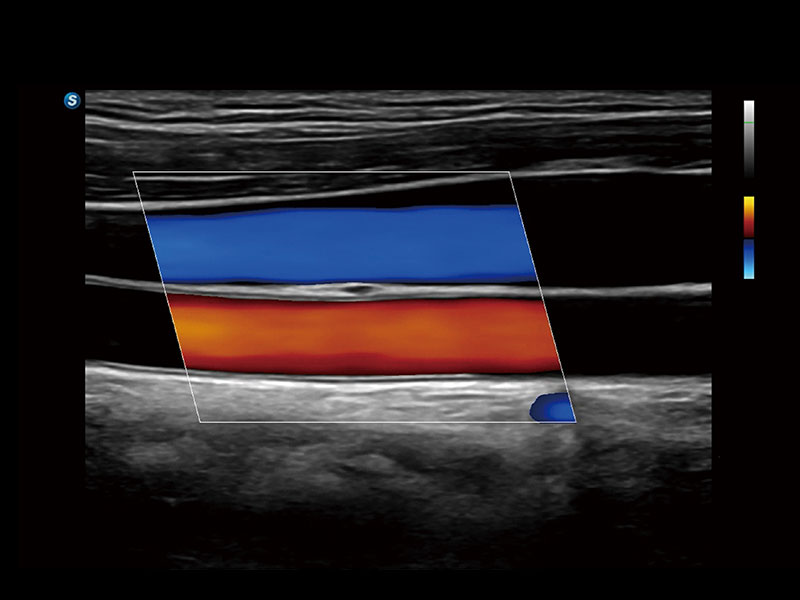

作为开立医疗全新打造的高端床旁笔记本超声,E11不仅具备卓越的图像质量,同时搭载全面高效的自动测量工具,助力医生实现更快速、更精准的床旁诊断。

信噪比提升

分辨率&均一性提升

帧频提升